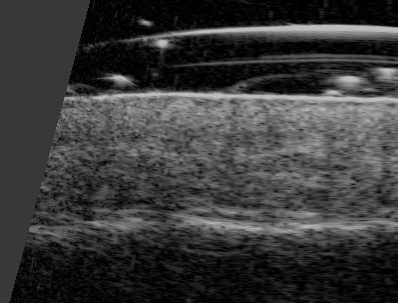

Badanie trychoskopowe,

pozwala na szczegółową ocenę stanu mieszków włosowych, łodyg włosów oraz skóry głowy. W przypadku pacjenta, lat 42, trichoskopia wykazała cechy charakterystyczne dla łysienia androgenowego, takie jak miniaturyzacja mieszków włosowych – proces, w którym mieszki stają się mniejsze i produkują cieńsze, słabsze włosy. Ponadto, badanie ujawniło oznaki reaktywności skóry, w tym nadwrażliwość, rumień oraz stan zapalny. Dzięki temu precyzyjnemu badaniu możliwe było dobranie optymalnej terapii, która nie tylko uspokoiła podrażnioną skórę, ale również stymulowała mieszki włosowe do wzrostu, co pozwoliło na zredukowanie przerzedzenia włosów i poprawę ich struktury.